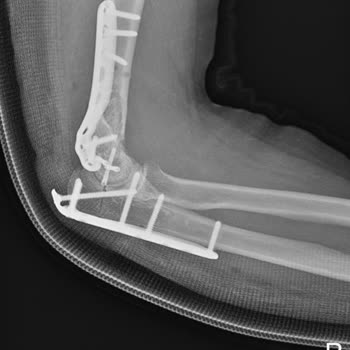

Fizik Tedavi Skandalı: Sağlam Dirsek Kemiği Kırıldı!

Ocak 2025 tarihinde fizik tedavi sırasında aşırı kuvvet uygulayarak sağlam dirsek kemiğimi kırdılar ve tekrar ameliyat olmak zorunda kaldım! Maddi ve manevi büyük zarar gördüm, ancak hatalarını kabul etmedikleri gibi muhatap bile olmadılar. Şikayetçiyim ve şu an davalık durumdayız. Önermiyorum. Zara...